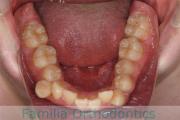

No.22V-449

- 主な症状:

- 上顎前突

- その他の症状:

- 叢生

- 年齢:

- 14歳

- 性別:

- 男性

- 抜歯部位

- 上:

- 44

- 下:

- 8448

- 主な使用装置:

- FEA

- 治療にかかった費用:

- 87万円

歯並びをきれいにしたいということで来院されました。上下左右から小臼歯を抜歯して、マルチブラケット法を行っています。2年弱、25回程度の通院が必要でした。

かなり強い叢生(でこぼこ、凹凸、ガタガタ)ですので、保定をしっかりしないと後戻りのリスクがあります。

- ≫治療前

上顎

下顎